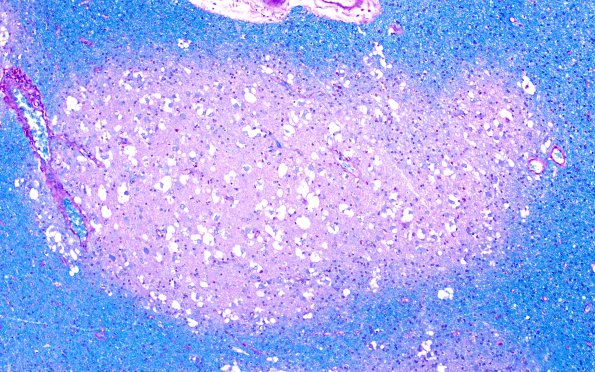

The relationship of nodules to the surrounding white matter is well seen in this LFB-PAS preparation